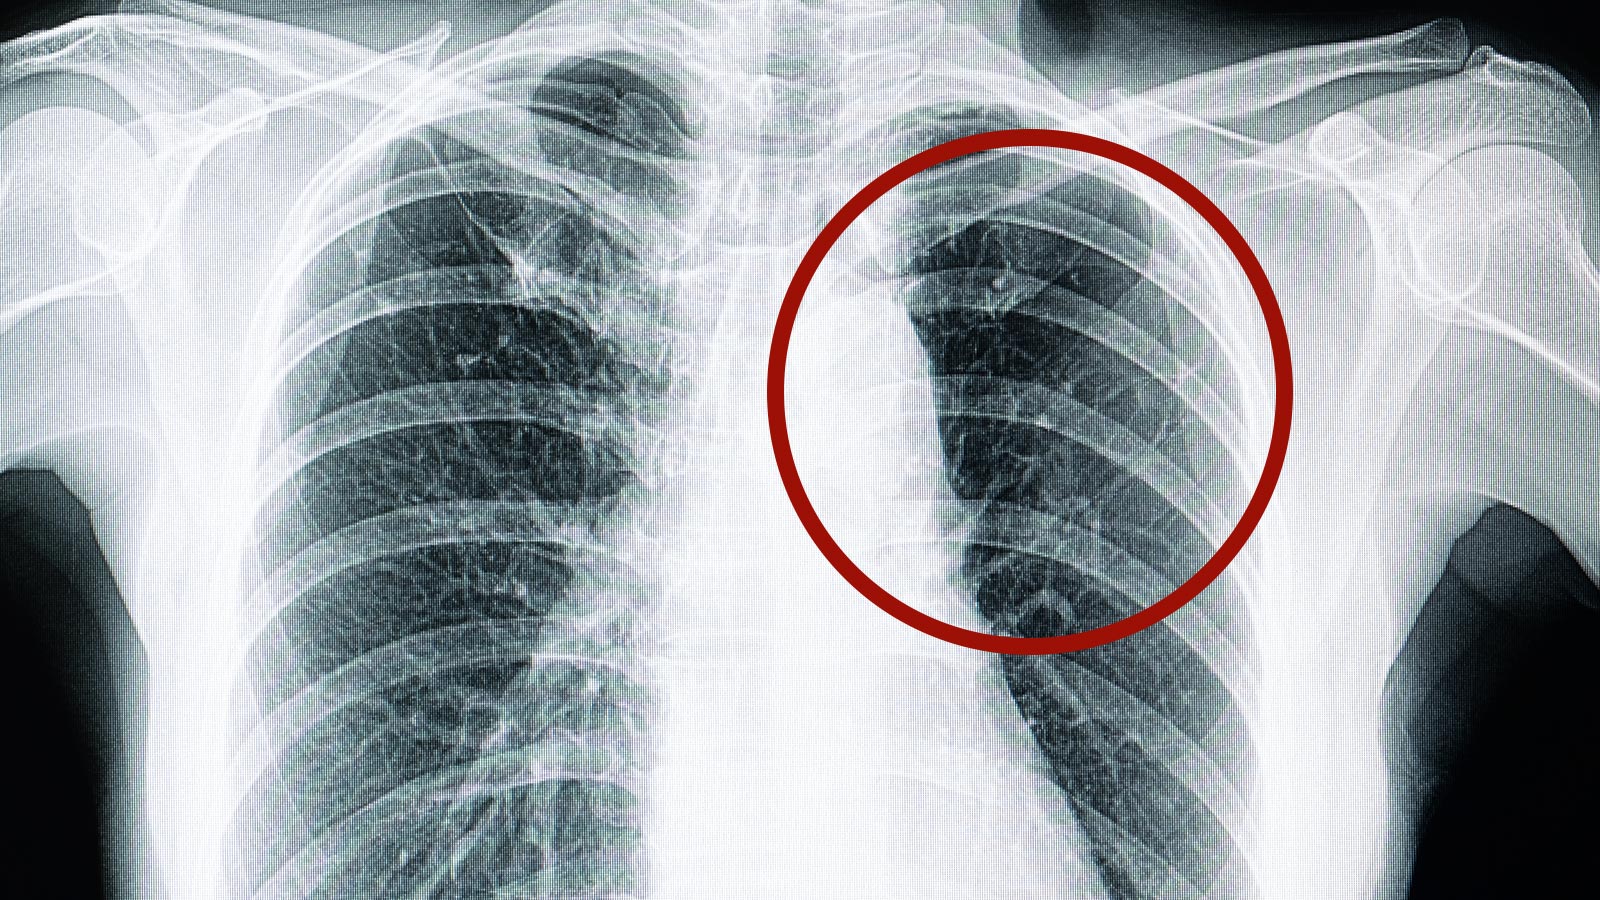

La fibrosis pulmonar es una enfermedad que afecta de forma progresiva los pulmones, que se endurecen y pierden su elasticidad, lo que lleva a reducir la capacidad respiratoria. En España afecta a unas 10.000 personas. Es un proceso grave, que en los casos más avanzados puede llegar a precisar incluso un trasplante pulmonar.